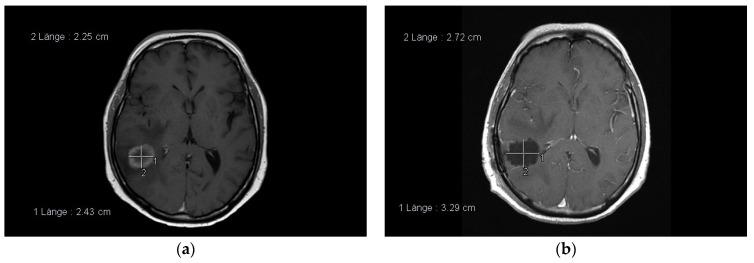

脑转移瘤的管理——神经外科方面的系统综述

The Management of Brain Metastases-Systematic Review of Neurosurgical Aspects.

The multidisciplinary management of patients with brain metastases (BM) consists of surgical resection, different radiation treatment modalities, cytotoxic chemotherapy, and targeted molecular treatment. This review presents the current state of neurosurgical technology applied to achieve maximal resection with minimal morbidity as a treatment paradigm in patients with BM. In addition, we discuss the contribution of neurosurgical resection on functional outcome, advanced systemic treatment strategies, and enhanced understanding of the tumor biology.

摘要

脑转移瘤(BM)患者的多学科管理包括手术切除、不同的放射治疗方式、细胞毒性化疗和靶向分子治疗。本综述介绍了应用神经外科技术以在发病率最低的情况下实现最大程度切除作为BM患者治疗模式的当前状态。此外,我们还讨论了神经外科切除对功能预后的贡献、先进的全身治疗策略以及对肿瘤生物学的深入理解。